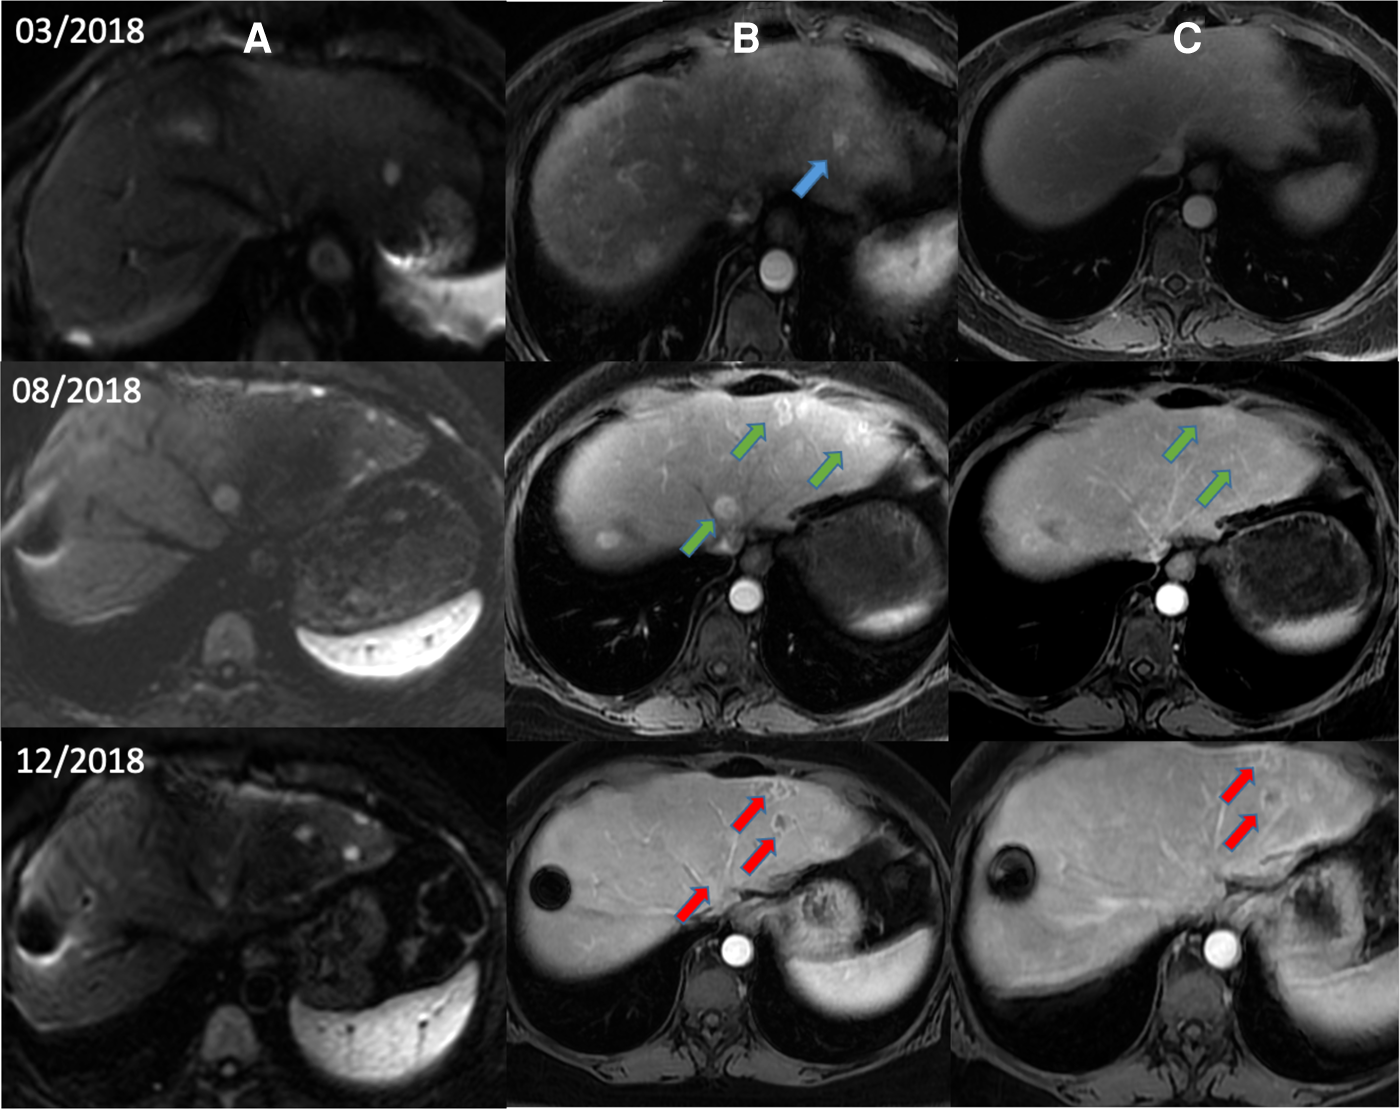

Figure 2

Magnetic resonance images from a patient with HCC after low-power amplitude-modulated radiofrequency electromagnetic field exposure. Diffusion-weighted imaging (A), arterial phase (B), and delayed phase (C) are shown. Patient with advanced HCC began treatment with sorafenib in March 2018 after diagnosis of recurrent HCC by diffusion and arterial phases (blue arrows). After documented radiological progression in August 2018 (green arrows), sorafenib was suspended and AutEMdev was started in 2-week intervals. In December 2018, lytic changes in the tumour lesions were observed by the arterial and delayed phases (red arrows). The patient was submitted to a surgical procedure to remove those lesions. Electronic micrographs of this patient are shown in Figure 3. HCC, hepatocellular carcinoma.